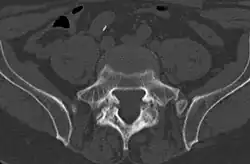

Spondylolysis is a bony defect or fracture within the pars interarticularis of the vertebral arch in the spinal column. The vast majority of spondylolysis occur in the lumbar vertebrae, however it can also be seen in cervical vertebrae.[3] The lumbar vertebra consist of a body, pedicle, lamina, pars interarticularis, transverse process, spinous process and superior and inferior articular facets, which form joints that link the vertebrae together. When examining the vertebra, the pars interarticularis is the bony segment between the superior and inferior articular facet joints located anterior to the lamina and posterior to the pedicle. Separation of the pars interarticularis occurs when spondylolysis is present in the spinal column.[14]

Computed tomography

Commonly known as a CT Scan or CAT scan, this form of imaging uses x-rays to produce multiple cross-sectional images, or "slices", through a part of the body. This allows a physician to evaluate the body in greater detail than an x-ray allows. For this reason the CT scan is much more accurate in detecting spondylolysis than an x-ray. Bone scintigraphy combined with CT scan is considered the reference standard, which means that it is best at detecting spondylolysis.[16][18]